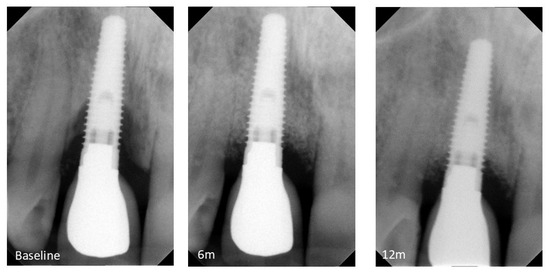

The goal of this paper was to determine the efficacy of the surgical treatment of two-wall peri-implant defects filled with L-PRF/xenograft block in the reduction of peri-implant marginal bone levels after 12 months. Ten patients with two-wall peri-implant defects were included. Patients received [...] Read more.

The goal of this paper was to determine the efficacy of the surgical treatment of two-wall peri-implant defects filled with L-PRF/xenograft block in the reduction of peri-implant marginal bone levels after 12 months. Ten patients with two-wall peri-implant defects were included. Patients received presurgical treatment followed by a surgical reconstructive intervention with bone blocks obtained by mixing bovine origin xenogeneic bone graft grains with L-PRF membranes. Patients were followed up at 3, 6, 9, and 12 months for oral hygiene and disease relapse evaluation and assessment of the primary outcome marginal bone levels (MBL) and clinical outcome variables such as probing depth (PD), bleeding on probing (BOP), and mucosal recession. Data was analyzed for changes between baseline and the 6- and 12-month follow-ups. Mean MBL was 5.1 ± 1.7 mm and 1.58 ± 0.92 mm at baseline and 6 months after the procedure, indicating a statistically significant decrease (p = 0.0005). At 12 months post-surgery, marginal bone levels remained stable at 1.8 ± 0.9 mm, with no statistically significant difference from the previous evaluation (p > 0.05). From baseline to 6 months there was also a statistically significant decrease in PD (from 8.07 ± 1.51 mm to 3.33 ± 0.59, p < 0.0001) and BOP (from 60.0% to 13.0% of affected surfaces, p < 0.001). No changes were observed from the intermediate to the 12-month follow-up (p > 0.05 for all variables). Full article